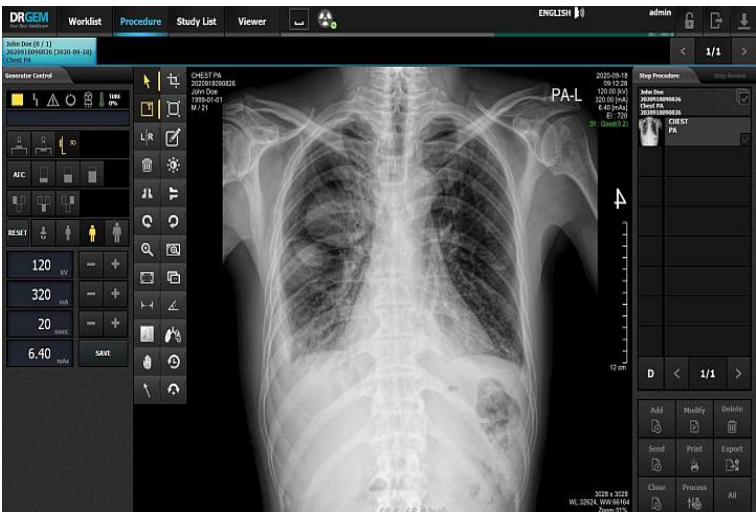

Передовые технологии рентгеновской диагностики RADMAX

Алгоритм обработки изображений DrGeGm RADMAX™ гарантирует точность и надёжность диагностики благодаря превосходному качеству и высокому разрешению снимков. Адаптивные фильтры и технологии обработки RADMAX™ позволяют получить превосходную детализацию снимков согласно 3000заложенных присетов по всем анатомическим областям человека.

Интуитивно понятный и удобный в использовании интерфейс АРМ лаборанта обеспечивает простоту управления системой. Благодаря продуманной

эргономике, все механические перемещения стойки доступны с полным контролем параметров экспозиции и фокусного расстояния, а так же углов положения излучателя к пациенту и цифровому приемнику.